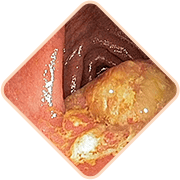

3 smrtonosne opasnosti od hemoroida ako se započne

Bilo što od sljedećeg može dovesti do iznenadne smrti pacijenta!

Izmet sadrži ogromnu količinu mikroba, bakterija i gljivica. Ako infekcija uđe u zdjelično tkivo i susjedne organe, moguća je opasna upala i trovanje krvi

Ispunjene žile hemoroidne kvržice vrlo su slabe. Često puknu. Stupanj gubitka krvi u ovom slučaju može biti takav da je potrebna transfuzija krvi

Krvni ugrušci nastaju u posudama. Ti krvni ugrušci mogu se odlomiti i začepiti žile unutarnjih organa, poremetiti cirkulaciju krvi i uzrokovati blokadu plućnih arterija. Velika vjerojatnost smrti